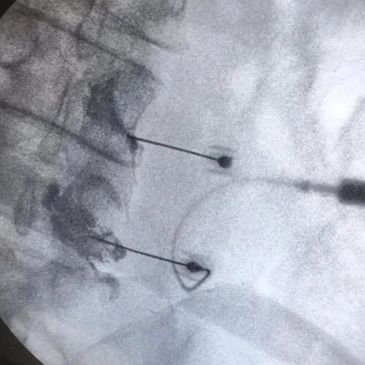

Bloqueos de dolor guiados por Rayo X para el manejo de dolor y aliviar s con tratamientos pare el dolor eficaces.

Inyecciones guiadas por sonografía o Rayos X para el manejo de dolor en articulaciones y tendones, incluyendo bloqueos de dolor para afecciones como el dolor de hombro, codo, mano, cadera, rodilla o pie, son tratamientos de dolor efectivos.